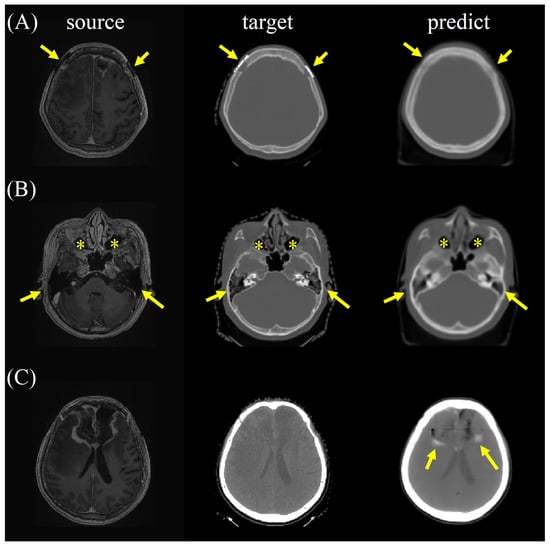

For synthetic CT, radiologists valued excellent satisfaction in spatial geometry and noise level, good satisfaction in contrast and artifacts, and fair imaging details for the bone and soft tissue window images (Supplementary Materials Tables S4 and S5). Higher satisfaction scores were observed on the bone window images than on the soft tissue window images for evaluation of the details, contrast, and artifact (Table 1). There was no statistically significant difference in synthetic CT on axial, coronal, or sagittal planes. The reader agreement rate was excellent in terms of spatial, detail, contrast, noise, and artifact in axial, coronal, and sagittal planes for both the bone and soft tissue window images from the synthetic CT. Interestingly, the metallic artifact was reduced, and the air density of the paranasal sinuses and mastoid air cells were well preserved on the bone window images of the synthetic CT (Figure 7a,b). Of note, perifocal hyperdensities on the soft tissue window images of the synthetic CT might lead to a false impression of intracranial hemorrhage, which should have been postoperative encephalomalacia and white matter edema (Figure 7c).

Figure 7. (A) The metallic artifact was reduced (arrows), and (B) the air density of the paranasal sinuses (asterisks) and mastoid air cells (arrows) were well preserved on the bone window images of the synthetic CT. (C) Perifocal hyperdensities (arrows) on the soft tissue window images of the synthetic CT might lead to a false impression of intracranial hemorrhage, which should have been postoperative encephalomalacia and white matter edema.